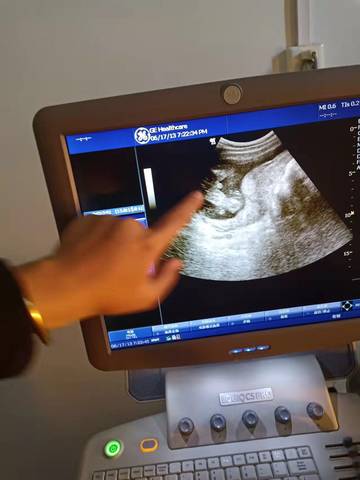

B超截图看看男孩女孩

journal_insert_pic_1687387447journal_insert_pic_1687387462

你好,对于宝宝是男孩女孩虽然很好奇,但是怀孕的单子、数据、表现是判断不出来的,在这也愿你心想事成。

你好。我们是判断不了男宝宝跟女宝宝的,孕期定期检查,我觉得宝宝健康就好的。祝心想事成 。